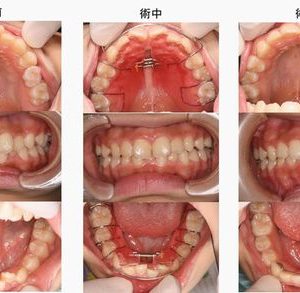

指しゃぶりをやめて6ヶ月(5歳、女の子、開咬)

5歳になっても指しゃぶりを続けていた女の子。上下の前歯が咬み合わない状態になっています。幼稚園の年長組に上がるタイミングで指しゃぶりをやめるようにトレーニングを行いました。しばらくして指しゃぶりをやめました。6ヶ月後には ...